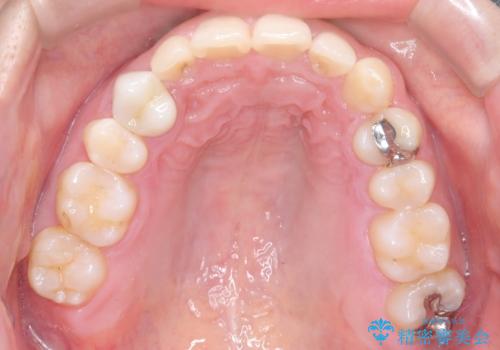

- 前歯の叢生(ガタつき)と、上下の噛み合わせが一部逆になっている反対咬合を主訴にご来院されました。精密検査の結果、前歯の移動だけでは不十分で、歯列全体のアーチを整えながらスペースを確保する必要があると診断。

中等度の症例に最適で最大26ステージ(※プランによる)のマウスピースが使用可能な**「インビザライン・モデレート」**を選択しました。これにより、抜歯をせずに歯列を横に広げ(側方拡大)、前歯を並べる十分なスペースを作りながら反対咬合を確実に改善する計画を立案しました。

反対咬合の解消: 内側に入っていた前歯を、マウスピースの力を利用して外側へ押し出しました。同時に、下顎の歯並びも微調整することで、スムーズに正常な噛み合わせへと誘導しました。